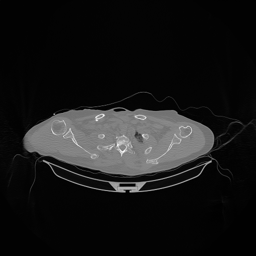

The results for simulated noisy data are shown in Fig. 2. The first and third rows display two representative slices from the test set, and the second and fourth rows present the corresponding error maps. The traditional WCE method suppresses cupping artifacts and recovers some missing anatomical structures but still shows noticeable deviations from the ground truth. Predictions from the four diffusion-based models demonstrate a markedly improved ability to restore anatomical structures. Among them, cDDPM fails to fully reconstruct the patient bed and retains residual noise in its outputs. This noise is attributable to an incomplete reverse denoising process rather than residual Poisson noise, as evidenced in our noise-free experiments (Fig. 5 in the Appendix). PatchDiffusion, diffusionGAN, and I2SB achieve similar visual quality, with I2SB producing the cleanest and most consistent reconstructions.

The experimental results on clinical head data are shown in Fig. 4. The reference images were reconstructed using the fast iterative shrinkage-thresholding algorithm (FISTA) with total variation regularization from non-truncated projection data. In the WCE reconstructions (Fig. 4(b)), severe truncation prevents accurate recovery of anatomical structures outside the FOV. Despite being trained solely on simulated data with a domain gap, all deep learning models can restore a substantial portion of the missing anatomy. Among them, the diffusion-based methods recover soft-tissue boundaries more faithfully than the conventional deep learning approach FBPConvNet, highlighting their stronger image generation capability. However, cDDPM reconstructions exhibit more noticeable noise than those from other methods, consistent with the simulated data results. The patchDiffusion model introduces artifacts within the FOV, likely due to its patch-wise processing strategy. While I2SB shares the same limitations as other diffusion models in perfectly restoring soft-tissue detail, it produces fewer residual noise patterns and fewer artifacts within the FOV boundaries. Overall, Fig. 4 demonstrates the strong efficacy of I2SB in reconstructing real CBCT data.